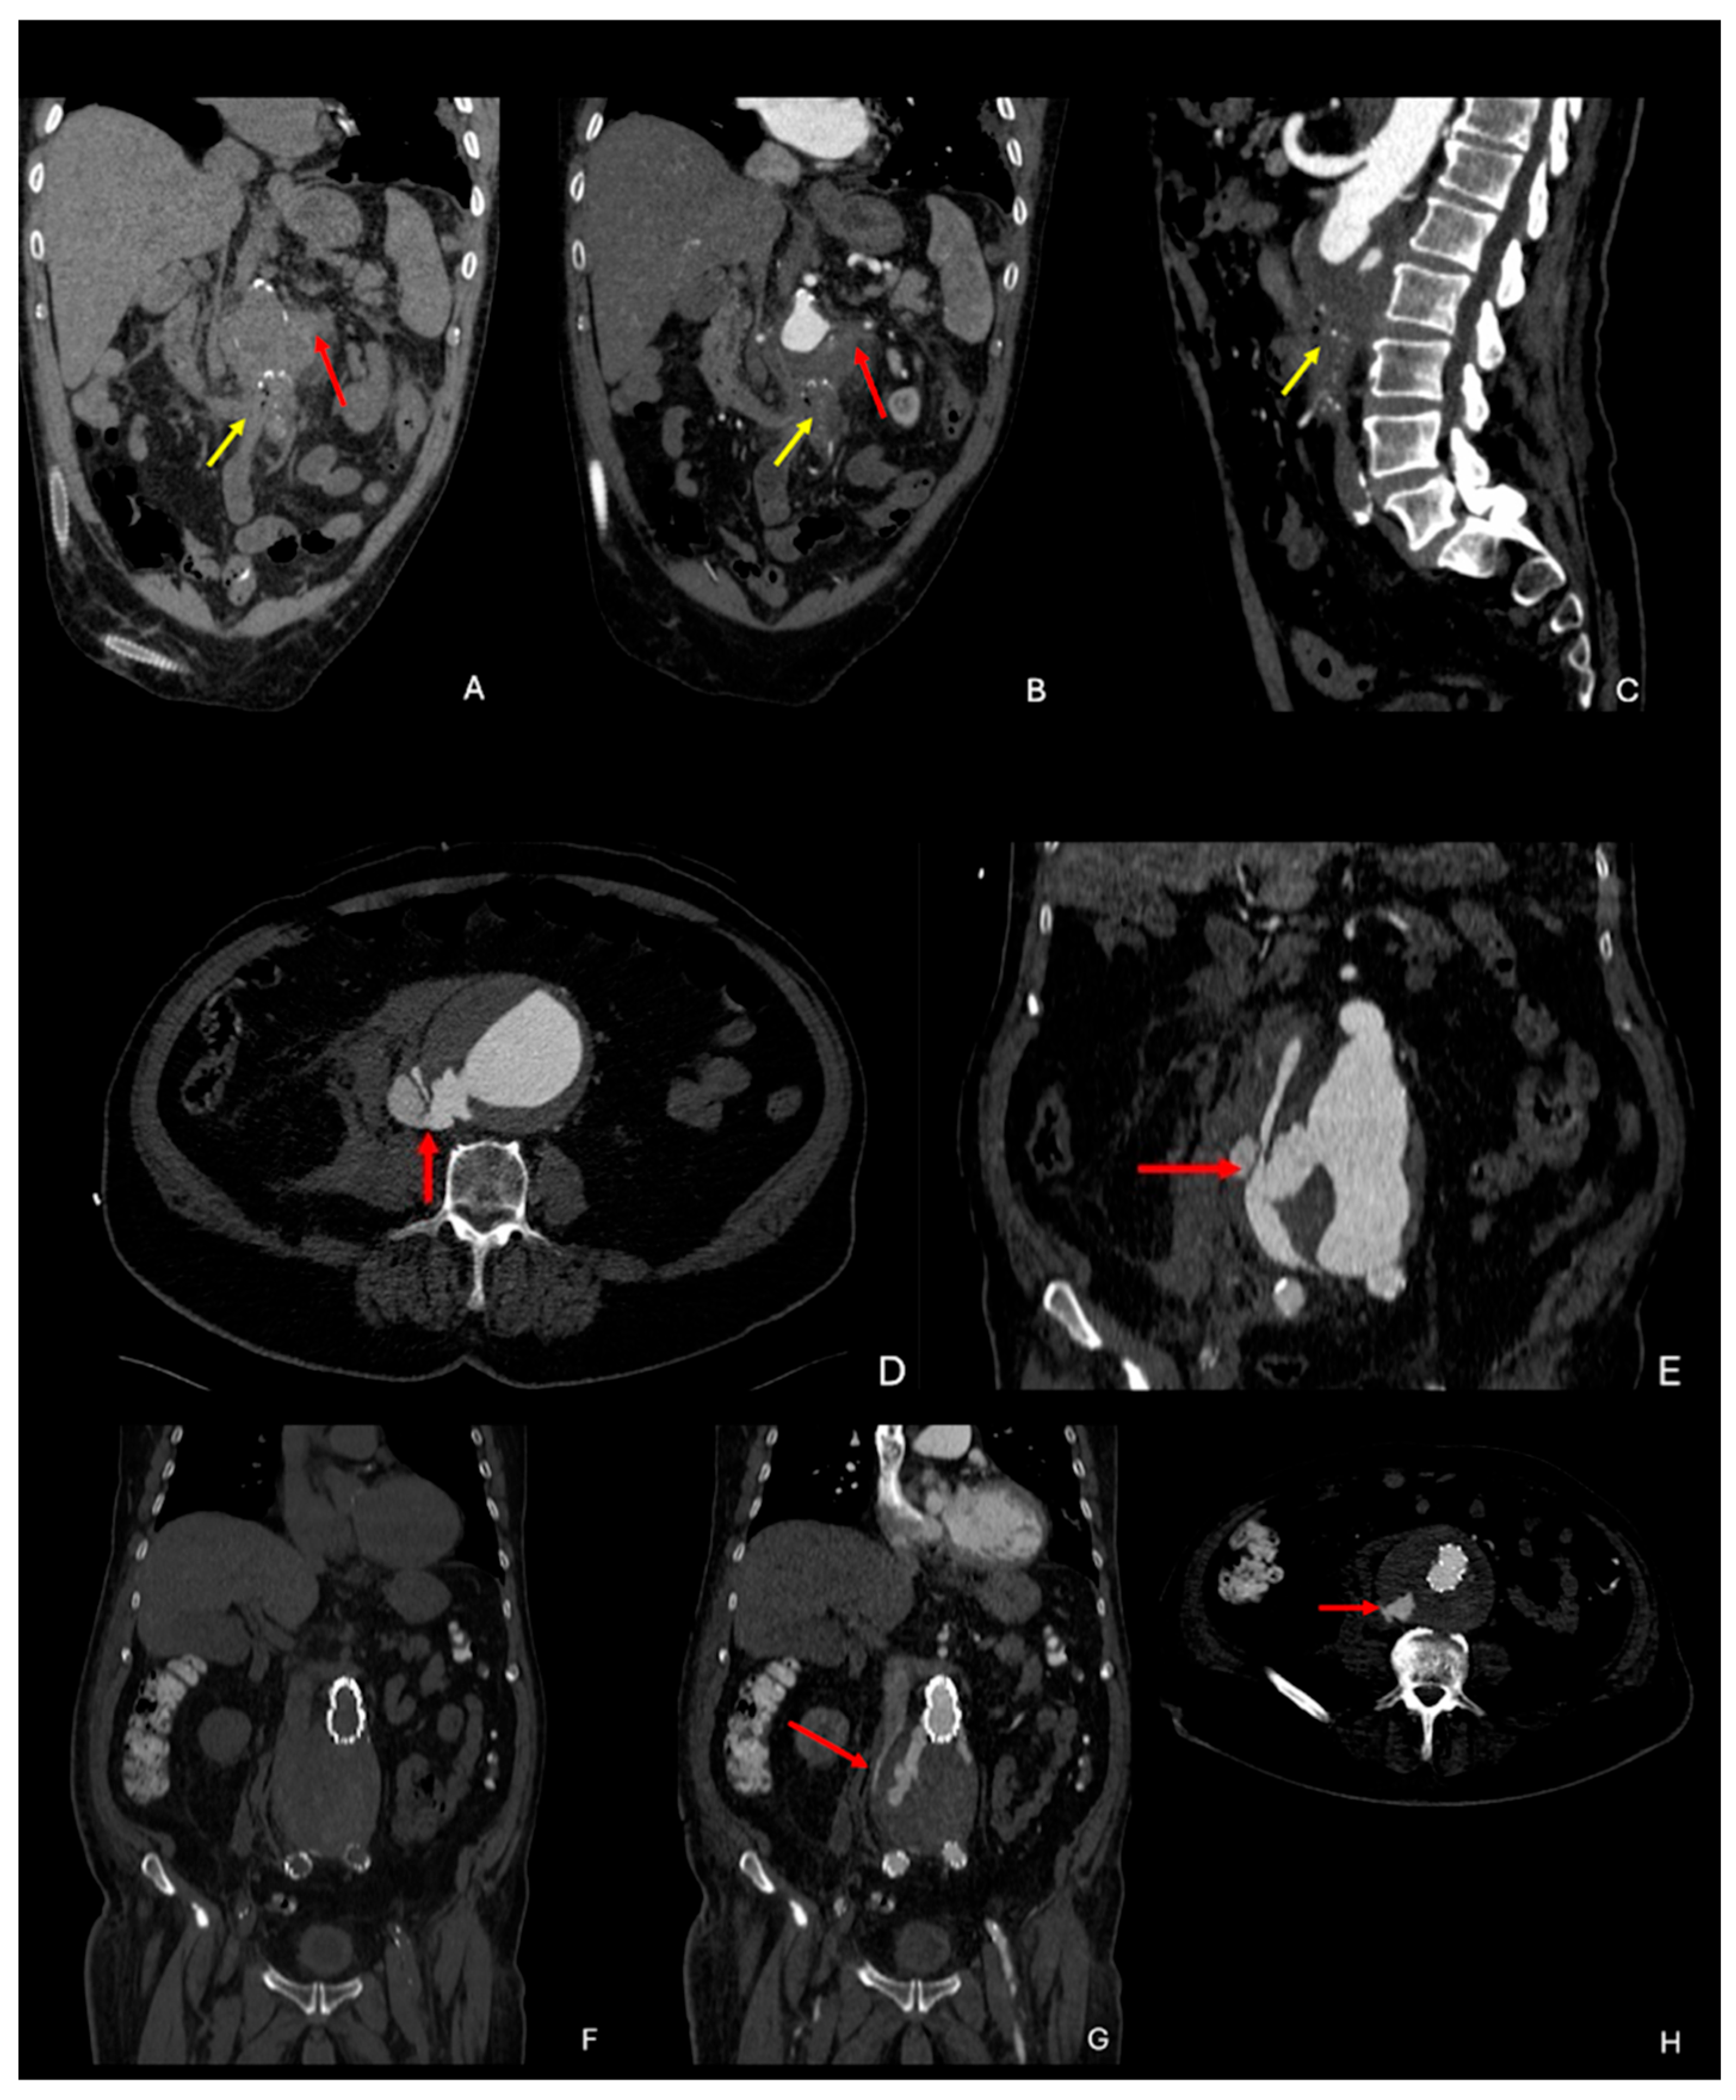

- Macedo, T.A.; Stanson, A.W.; Oderich, G.S.; Johnson, C.M.; Panneton, J.M.; Tie, M.L. Infected Aortic Aneurysms: Imaging Findings. Radiology 2004, 231, 250–257. [Google Scholar] [CrossRef]

- Lee, W.-K.; Mossop, P.J.; Little, A.F.; Fitt, G.J.; Vrazas, J.I.; Hoang, J.K.; Hennessy, O.F. Infected (Mycotic) Aneurysms: Spectrum of Imaging Appearances and Management. RadioGraphics 2008, 28, 1853–1868. [Google Scholar] [CrossRef] [PubMed]

- Restrepo, C.S.; Ocazionez, D.; Suri, R.; Vargas, D. Aortitis: Imaging Spectrum of the Infectious and Inflammatory Conditions of the Aorta. RadioGraphics 2011, 31, 435–451. [Google Scholar] [CrossRef] [PubMed]

- Ishizaka, N.; Sohmiya, K.; Miyamura, M.; Umeda, T.; Tsuji, M.; Katsumata, T.; Miyata, T. Infected aortic aneurysm and inflammatory aortic aneurysm—In search of an optimal differential diagnosis. J. Cardiol. 2012, 59, 123–131. [Google Scholar] [CrossRef]

- Tang, T.; Boyle, J.R.; Dixon, A.K.; Varty, K. Inflammatory Abdominal Aortic Aneurysms. Eur. J. Vasc. Endovasc. Surg. 2005, 29, 353–362. [Google Scholar] [CrossRef]

- Hellmann, D.B.; Grand, D.J.; Freischlag, J.A. Inflammatory Abdominal Aortic Aneurysm. JAMA 2007, 297, 395. [Google Scholar] [CrossRef]